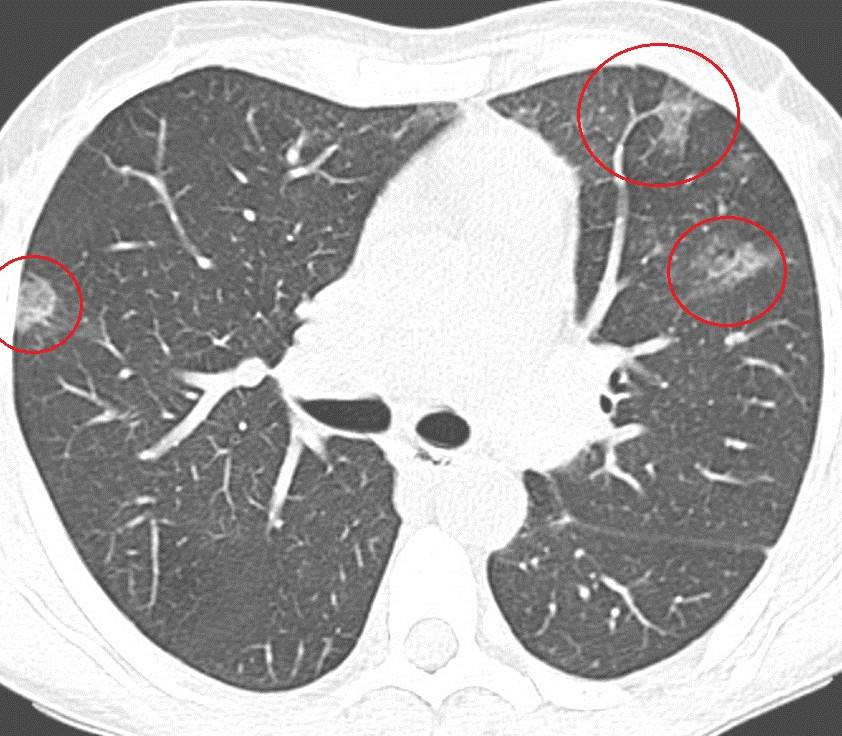

Эффект матового стекла

О воспалительном процессе в легких свидетельствуют хрипы, выявляемые при прослушивании пациента фонендоскопом, а также результаты рентгенографии легких. Для подтверждения вирусного происхождения пневмонии проводится исследование мокроты. По результатам лабораторных исследований в крови обнаруживается повышение титров антител к вирусному агенту.